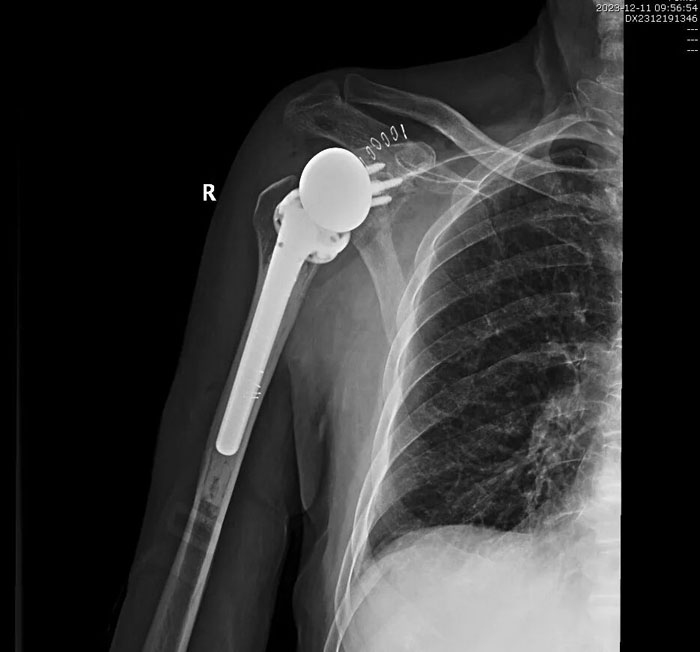

手術歷時2個小時順利完成,術后患者恢復良好,無并發(fā)癥發(fā)生,右肩關節(jié)功能明顯改善,患者對手術療效滿意。目前,患者已好轉(zhuǎn)出院,居家進行功能康復鍛煉中。

術后